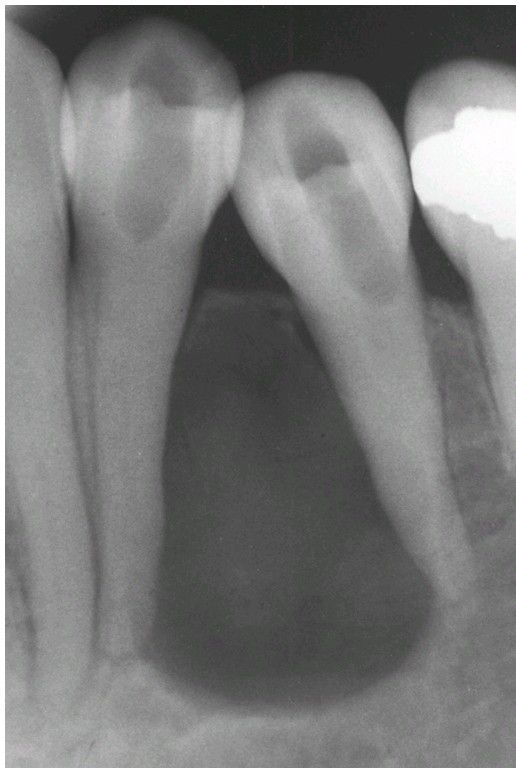

Lateral Periodontal Cyst.

A larger lesion causing root divergence.